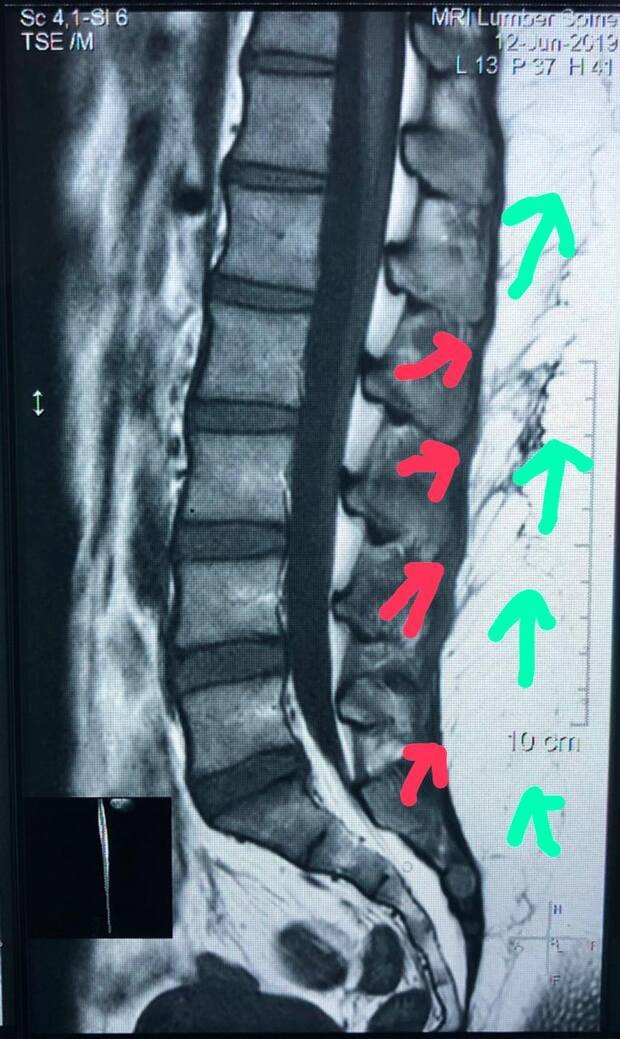

Upon careful examination of my spine, vertebra(e) (posture), and muscle/muscle mass, I am confident that the following vertebra(e) in my body are underdeveloped if not undeveloped: thoracic 5, thoracic 11, thoracic 12, lumbar 1, lumbar 2, lumbar 3, lumbar 4, lumbar 5, as best I can surmise. I am confident I am a Body Type Two (BT2) because I have between (1) and eight (8) vertebrae undeveloped. I am quite sure my body does not look identical to a Body Type One (BT1) with all muscles developed & defined. My body has not always had the fully developed BT1 classic arch, dimples, vertebrae (posture), and muscle mass. I am certain I do not have the fully developed BT1 classic arch and dimples, which strengthens my belief I'm not a BT1.

On average, I do not experience back aches and pain. I feel back aches and pains in my body in relation to: thoracic 11, thoracic 12, lumbar 1, lumbar 2, lumbar 3, lumbar 4, lumbar 5, and it is directly relative to my Body Type Two (BT2).